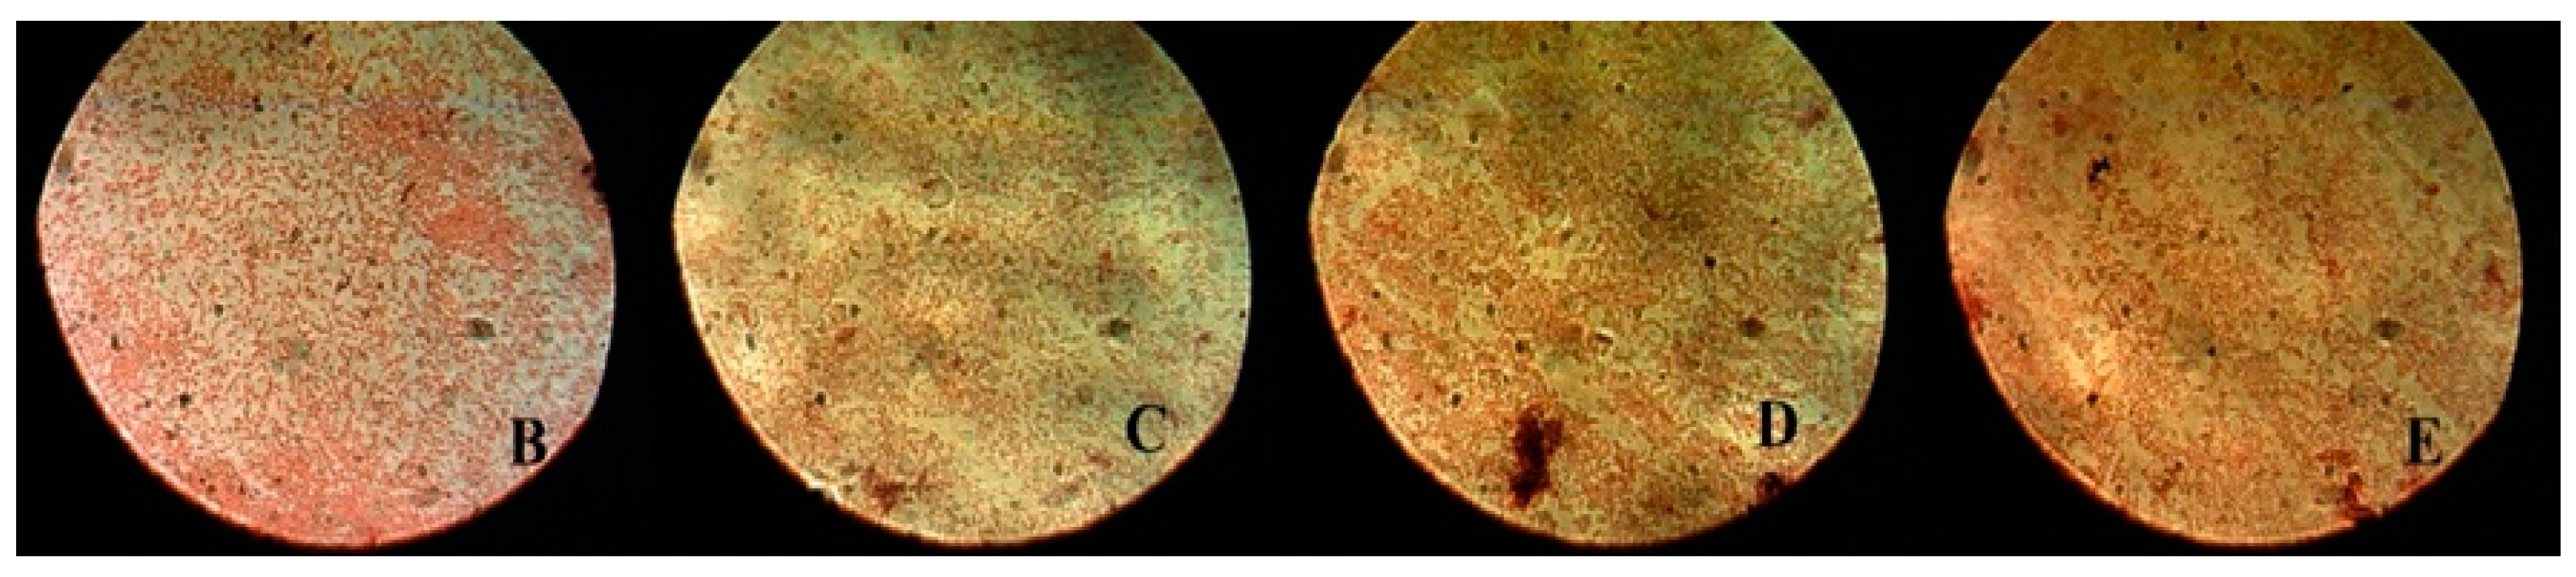

After counting the bacterial colonies, the samples were examined using an optical microscope (OPTIKA, B-600Tiph, Italy, 100×/1.25× oil PH, PLAN) in order to characterize the bacterial colonies. The bacterial colonies were evaluated in two stages: the first after bacterial inoculation for groups B, C, D, and E (Figure 4) and the second after applying all the interventions: MB, MB + PDT, CHL–PC, CHL–PC + PDT, and 2% CHX (Figure 5).

Figure 5. Characterization of bacterial colonies after MB, MB + PDT, CHL–PC, CHL–PC + PDT, and 2% CHX experimental treatments using an optical microscope (OPTIKA, B-600Tiph, Italy, 100×/1.25× oil PH, PLAN).